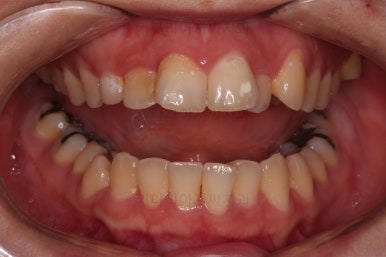

전후 비교입니다.

입매도 약간 나와있던 윗입술이 들어가면서 턱끝의 위치나 느낌도 같이 바뀌었고요.

웃을 때 보이는 치아의 가지런한 느낌과 뻗친 정도는 매우 좋아졌습니다.